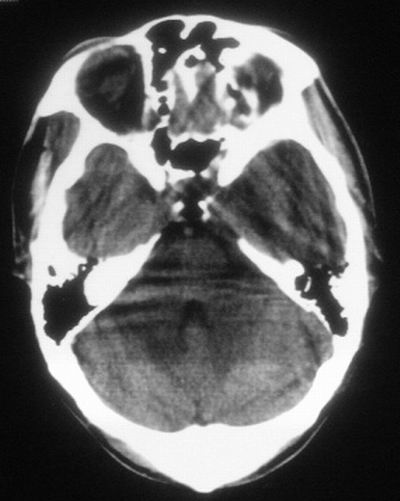

患者,男,30岁,右侧面部麻木,右上肢活动受限27小时。pe:神清、呼吸平稳,口角左歪,右上肢活动受限,右手掌握力消失,右侧躯体痛觉减退。

第一次颅脑ct扫描:左侧额顶叶血肿。